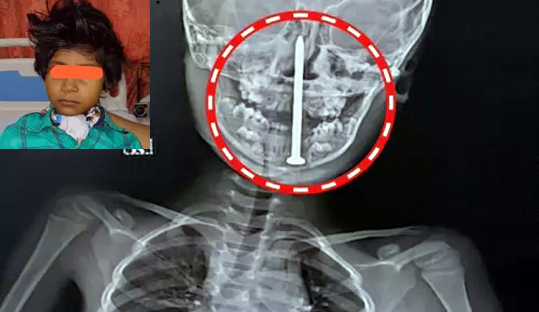

लखनऊ के KGMU ट्रॉमा सेंटर में बलरामपुर की 7 साल की बच्ची को नई जिंदगी मिली है. उसकी गर्दन और…